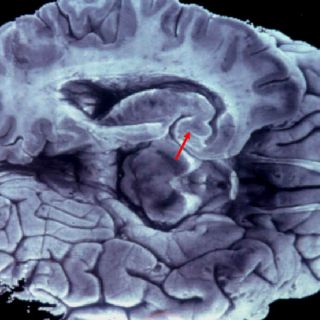

LONDRES, INGLATERRA (06/ENE/2012).- La pérdida de memoria y otras funciones cerebrales puede comenzar a los 45 años, lo que implica un gran desafío para los científicos que buscan nuevas formas de detener el avance de la demencia en la población, informaron investigadores.

El hallazgo de un estudio de 10 años de duración sobre más de siete mil trabajadores estatales de Gran Bretaña contradice las teorías previas de que el deterioro cognitivo no se inicia antes de los 60 años y podría tener implicancias de largo alcance en la investigación de la demencia.